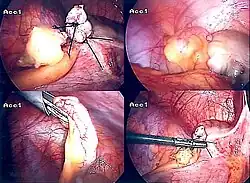

Диагностическая лапароскопия показана в сомнительных случаях, может переходить в лечебную лапароскопию при технической возможности, когда имеются условия для лапароскопической аппендэктомии; требуется письменное согласие пациента на удаление червеобразного отростка.